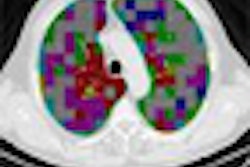

In the July issue of Hypertension, Dr. Guo of the University of Gothenburg, Sweden, and colleagues report on their analysis of data from 539 women who belong to a cohort followed since 1968. The women underwent CT brain scans in 1992 and/or 2000. Blood pressure information had been regularly recorded throughout follow-up.

The team found that the presence and severity of white-matter lesions on CT scans were associated with higher diastolic blood pressure and mean arterial pressure at each examination, but not with systolic blood pressure and pulse pressure.